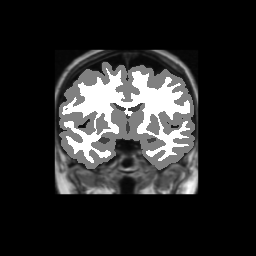

Test/Retest Reliability

FSL was run on each scan in the Brain Segmentation Testing Protocol (BSTP) between-scanner test/retest dataset. Select a subject below to see volumes for each subject across the subject's scans.